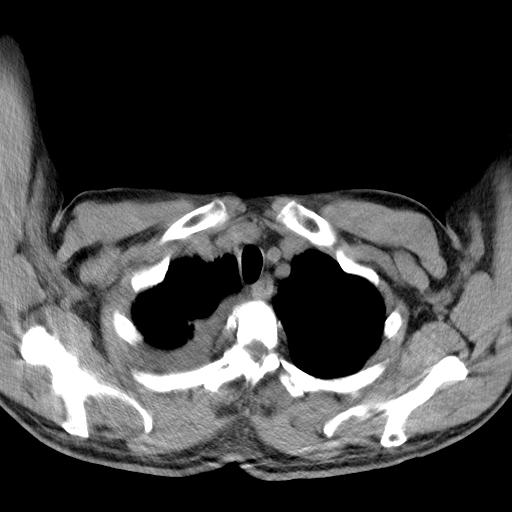

以下是引用zjzjr在2010-3-21 17:39:00的发言:[br]右下中心型肺癌并阻塞性肺炎/不张,纵膈淋巴结肿大,右侧大量胸腔积液,左侧少量胸腔积液

以下是引用zxl51642在2010-3-21 17:06:00的发言:[br]右下中心型肺癌并阻塞性肺炎/不张,纵膈淋巴结肿大,右侧大量胸腔积液,左侧少量胸腔积液,少量腹水。建议纤维支气管镜进一步检查。